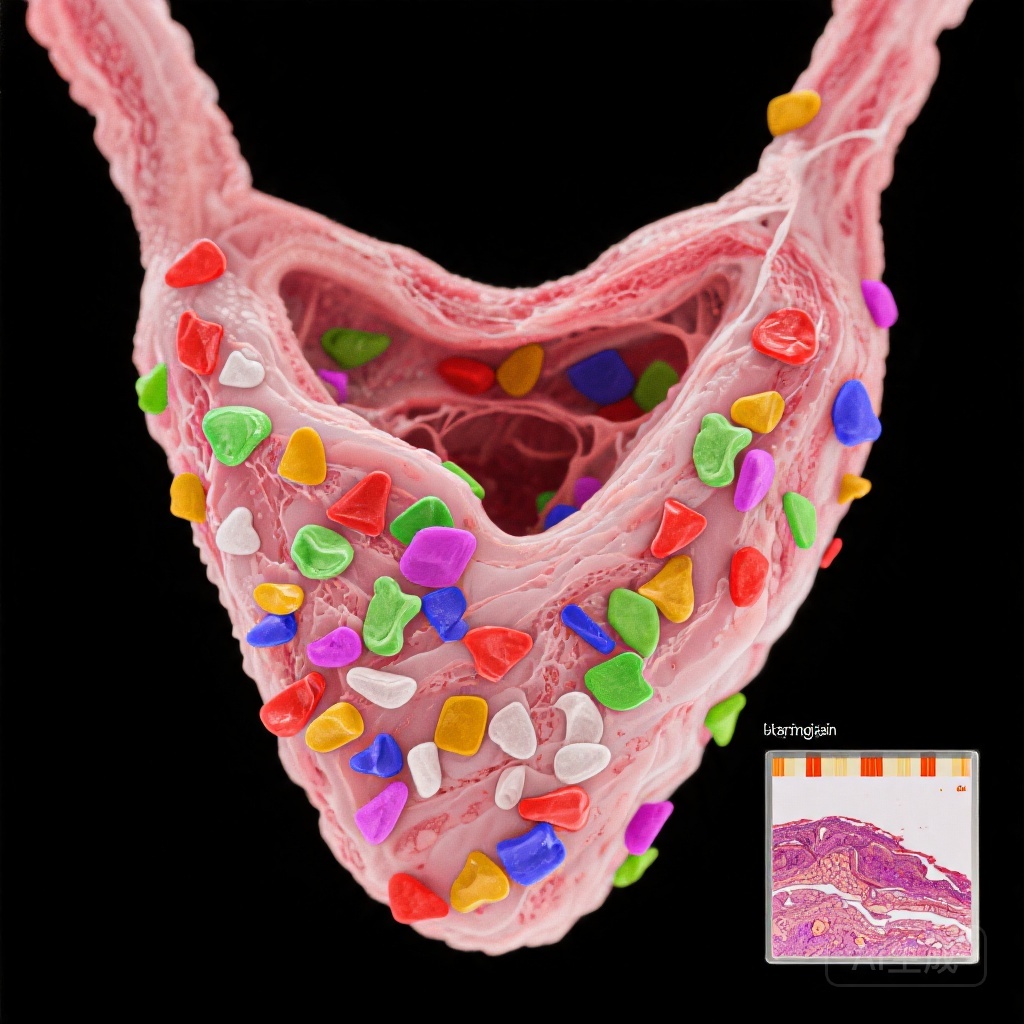

Nghiên cứu này so sánh mô tuyến giáp từ 29 bệnh nhân AIT được xác nhận qua hình ảnh học và 29 đối chứng cùng độ tuổi và giới tính có u tuyến giáp lành tính. MPs được định lượng bằng phương pháp nhiệt phân-gas sắc ký-chromatography-mass spectrometry (Py-GC/MS) và đặc trưng thông qua vi quang phổ Raman và vi kính điện tử quét (SEM).

Tổng nồng độ MPs đáng kể cao hơn ở bệnh nhân AIT (trung vị: 19,9 μg/g so với 1,9 μg/g; p=0,012), với PVC là polyme chiếm ưu thế. Vi quang phổ Raman cho thấy số lượng MPs cao hơn trong mô AIT (172 so với 50,2 đơn vị/g, p=0,037), với kích thước hạt từ 33,9 đến 1467 µm. Đặc điểm hình thái (kích thước, hình dạng, màu sắc) không khác biệt giữa các nhóm.